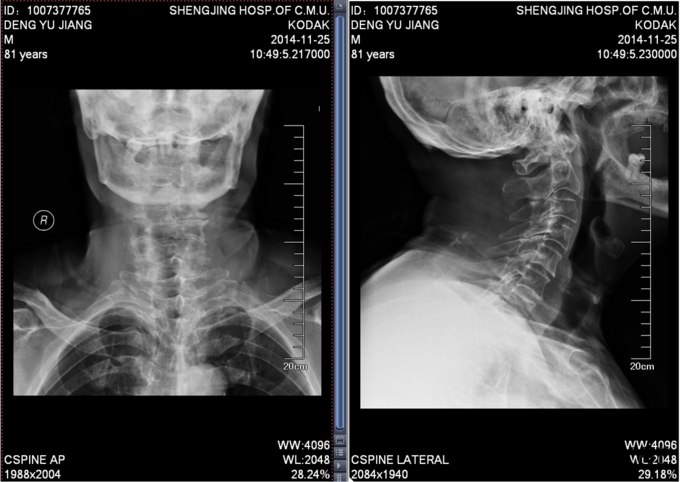

患者男,81岁,自述于1个月前出现双上肢感觉减退,发胀,以左侧为重,后来加重,左侧握力减退,于201医院就诊,行颈椎MR检查,提示为颈3-4、4-5间盘突出,为求进一步治疗就诊于我院,患者病来饮食、睡眠佳。大小便正常,体重无明显变化。

颈椎生理弯曲消失,活动度正常。双上肢感觉减退。双手握力(R5级,L4级),伸肘肌力(R5级,L5级),屈肘肌力(R5级,L5级),Hoffman(R-,L+)桡动脉搏动有力,末梢血运良。